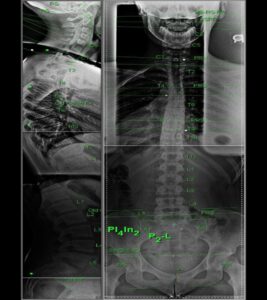

Raio-X

As radiografias fazem mais do que apenas revelar patologia. Ajudam-me a determinar exactamente como e onde ajustar. Isto inclui:

• Identificar o ponto de contacto preciso

• Saber qual o lado da articulação a estabilizar e qual a ajustar

• Escolher a linha óptima

O objectivo não é simplesmente “endireitar” a tua coluna, mas restaurar a sua função natural, respeitando o que é normal para a tua estrutura individual.

A maioria das pessoas nunca teve a sua coluna analisada desta forma. Tiveram exames para descartar problemas. Isto é diferente — é uma análise para encontrar o ponto exacto de correcção.